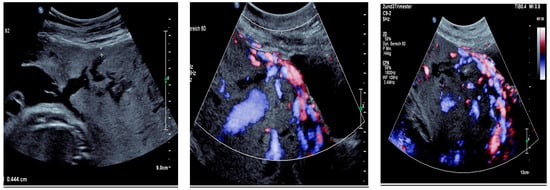

Sonographic findings (Figure 2):

Figure 2.

Irregular and large lacunae: Sonographic imaging reveals irregularly shaped and enlarged lacunae within the placenta. Hypervascularity: Increased vascularity is observed within the placenta, indicating abnormal blood flow. Turbulent flow in lacunae: Doppler imaging demonstrates turbulent blood flow within the lacunae, suggestive of abnormal vascularization. Changes in diameter: Variations in the diameter of lacunae may be noted on sonographic examination, reflecting the dynamic nature of placental vascularization in PAS.

Sonographic findings (Figure 4):

Figure 4.

shows suspected placenta increta with dehiscence in the area of scar tissue from the previous uterotomy.